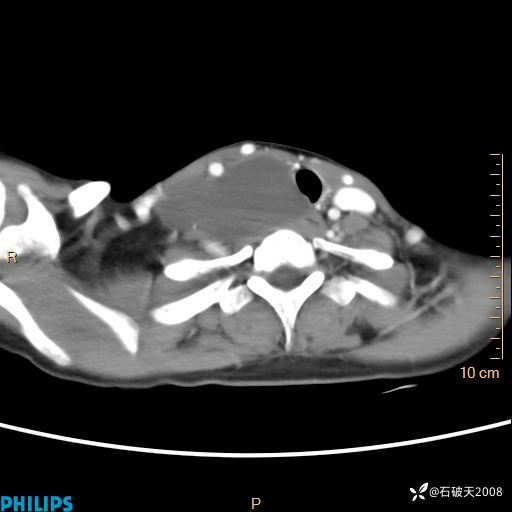

影像诊断要密切结合临床,真的很有必要(病理已公布)

女 21岁 主 诉:发现右侧颈部肿物18年余。

现病史:18年余前患者无明显诱因发现颈部偏右侧有一肿物,具体大小不明确,咳嗽、憋气时肿物增大,局部无疼痛,无吞咽不适,无胸闷及呼吸困难,至当地医院检查考虑良性病变(具体不详)并未做特殊处理,现患者自觉肿物随年龄增长而进一步变大,今日至我院行颈部CT平扫+增强提示:1.右侧颈根部、锁骨上窝及纵隔内异常密度影,考虑良性病变,淋巴管瘤?囊肿?请结合临床。2.双侧颈部小淋巴结。建议结合临床及其他相关检查。现为行进一步治疗,门诊以“颈部局部肿物”为诊断收住我科,发病来患者神志清,精神可,饮食睡眠可,大小便正常,体重无下降。

平扫